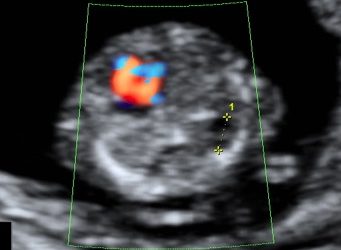

How To Do Giugno 2020: le arterie uterine

Finalmente on line il nuovo video "How to do" del mese di Giugno, sul campionamento delle arterie uterine! Grazie a...